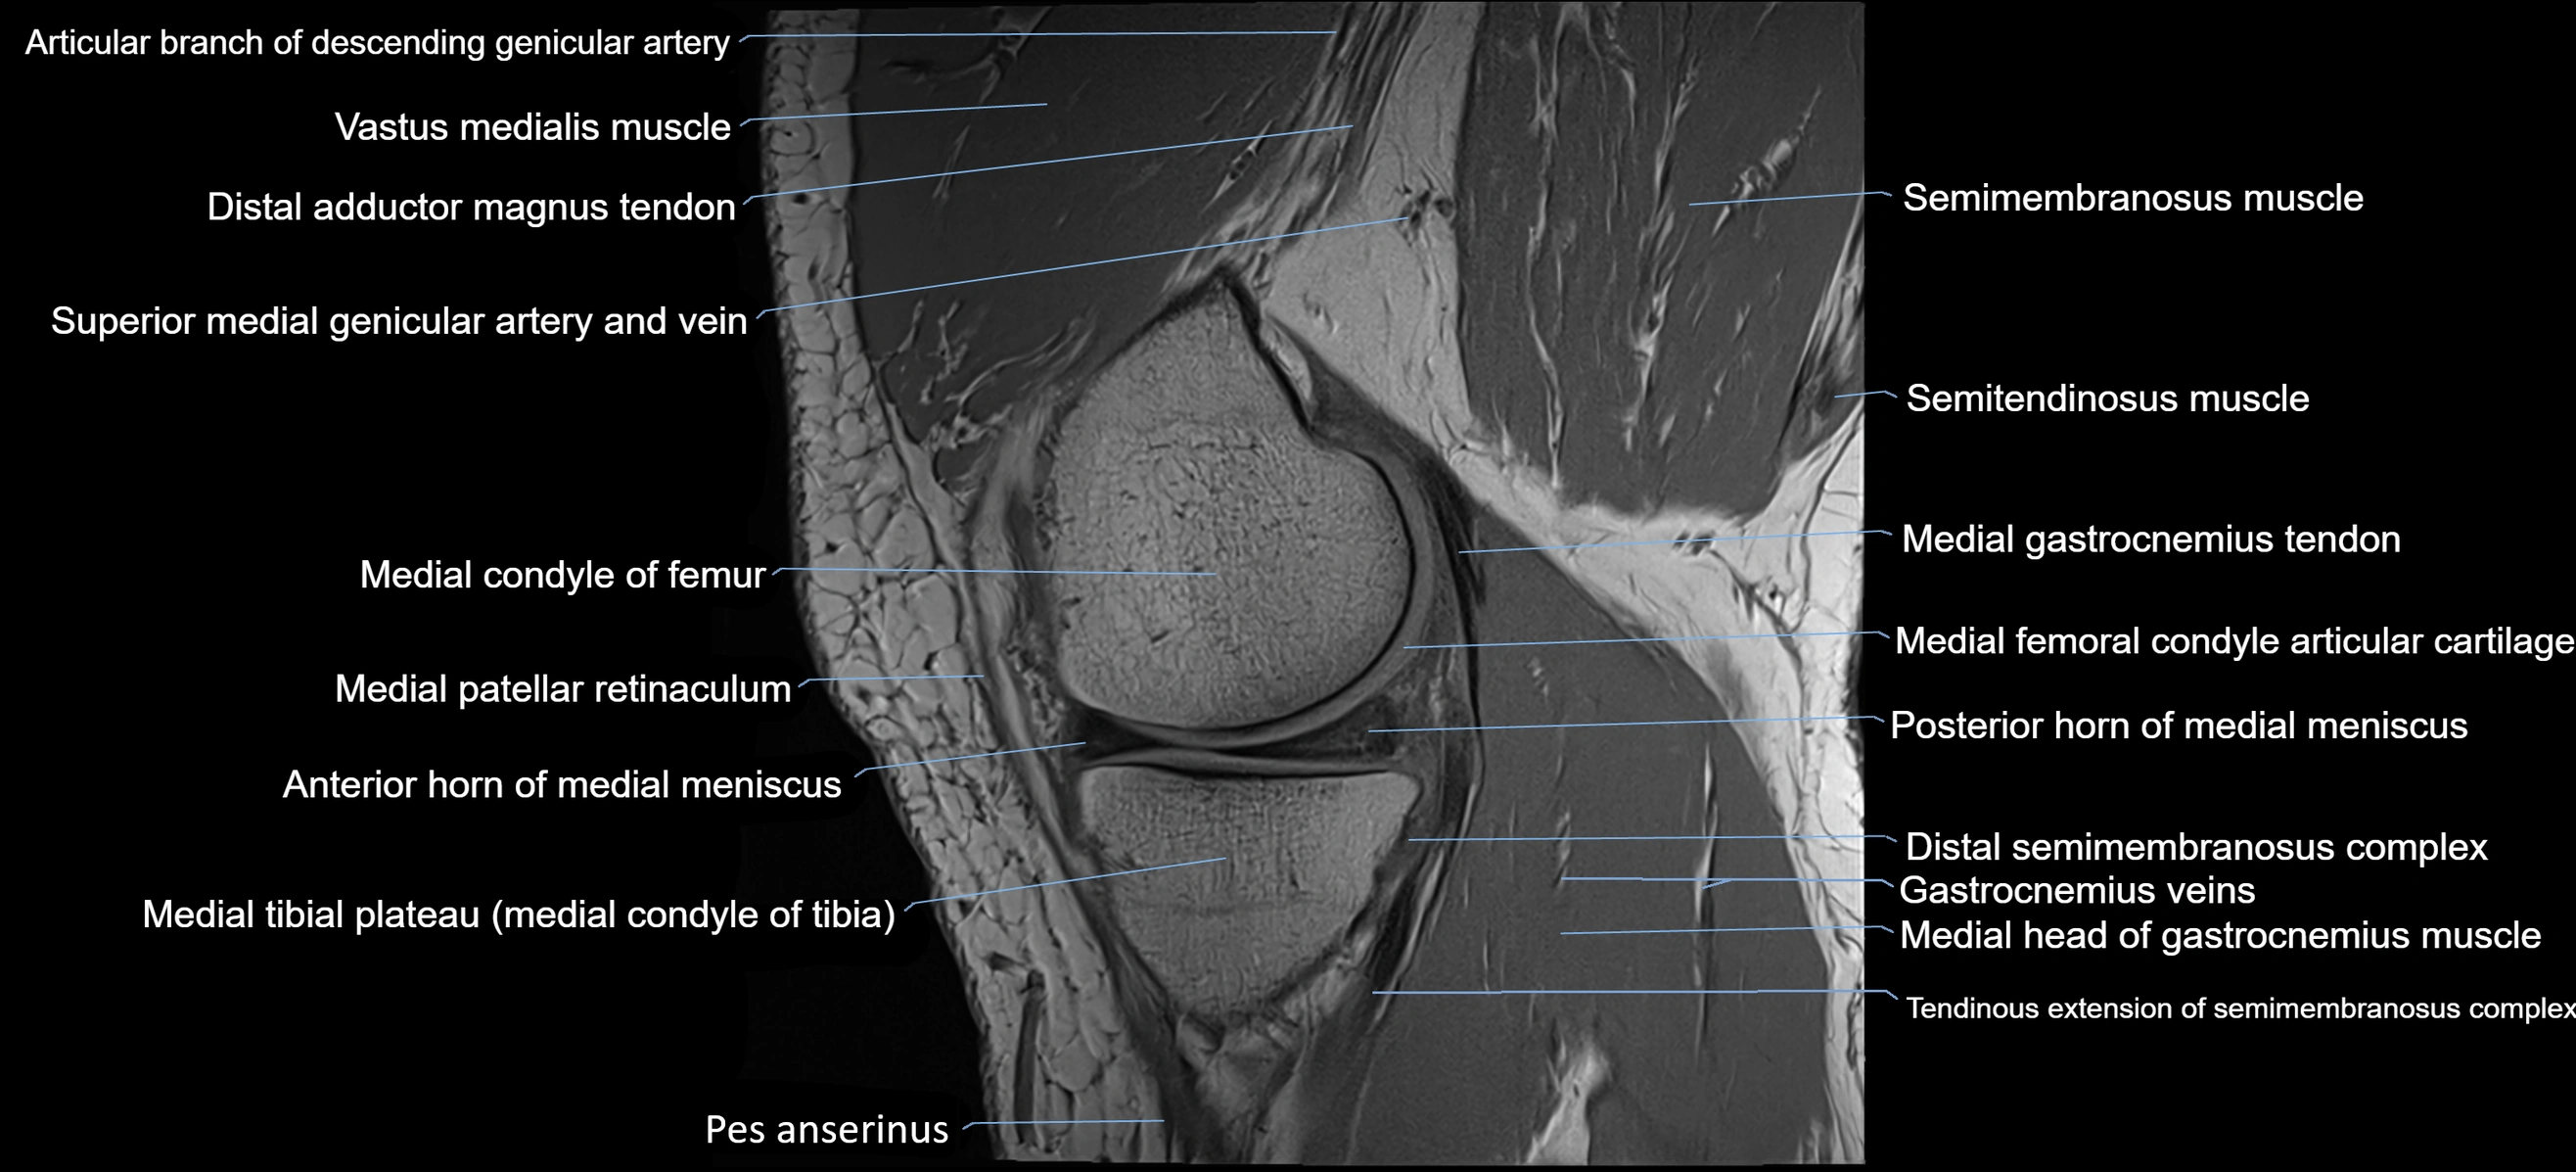

- Medial condyle of femur

- Medial condyle of tibia

- Medial gastrocnemius tendon

- Medial head of gastrocnemius muscle

- Medial patellar retinaculum

- Medial patellofemoral ligament

- Medial tibial plateau

- Posterior horn of medial meniscus

- Anterior horn of medial meniscus

- Semimembranosus muscle

- Semitendinosus muscle

- Gracilis tendon (Distal)

- Sartorius tendon (Distal)

- Popliteal–Saphenous perforating veins

- Distal semimembranosus tendon